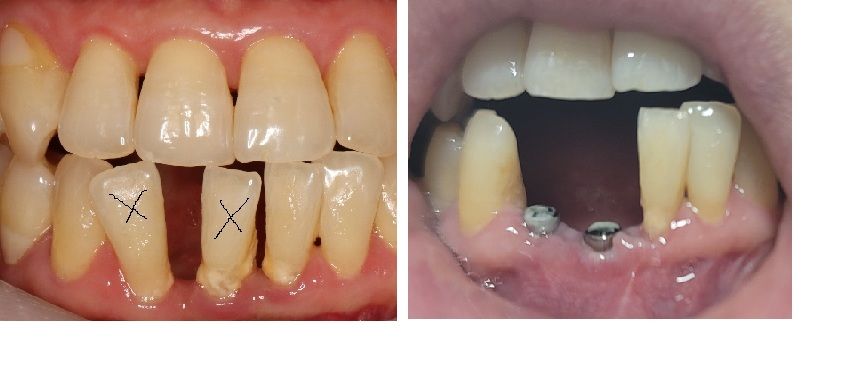

앞니는 30대 초중반부터 상태가 안좋았으며, 대학병원 치주과에서 치주소파술을 받은 뒤, 10년이 넘는 시간동안 나름 열심히 관리를 하면서 조심스럽게 사용을 하였습니다. 그러나, 더이상 앞니가 기능을 하지 못하고 흔들림이 심해지면서, 흔들림으로 치실이나 치간칫솔을 사용하기 어려워지면서, 치석도 엄청 끼고 결국 임플란트를 결심하게 되었습니다. 임플란트를 하기 전 앞니 상태입니다.

위의 사진에서 x표시 있는 2개의 치아를 1차 수술에서 발치하고 바로 임플란트식립+인공뼈 추가하고, 힐링 어버트먼트까지 부착을 하였습니다. 1차 수술 당시에는 힐링어버트먼트가 잇몸으로 많이 가려진 상태였습니다.

2) 수술 전후를 비교해보면.... 사진 기준으로 좌측은 잇몸이 살짝 올라온 것 같고, 우측은 아쉽게도 큰 변화는 없는거 같구요... 뼈이식으로 잇몸이 조금 재생되었다고 판단해도 될까요?

• 2번 째 사진

• 3번 째 사진